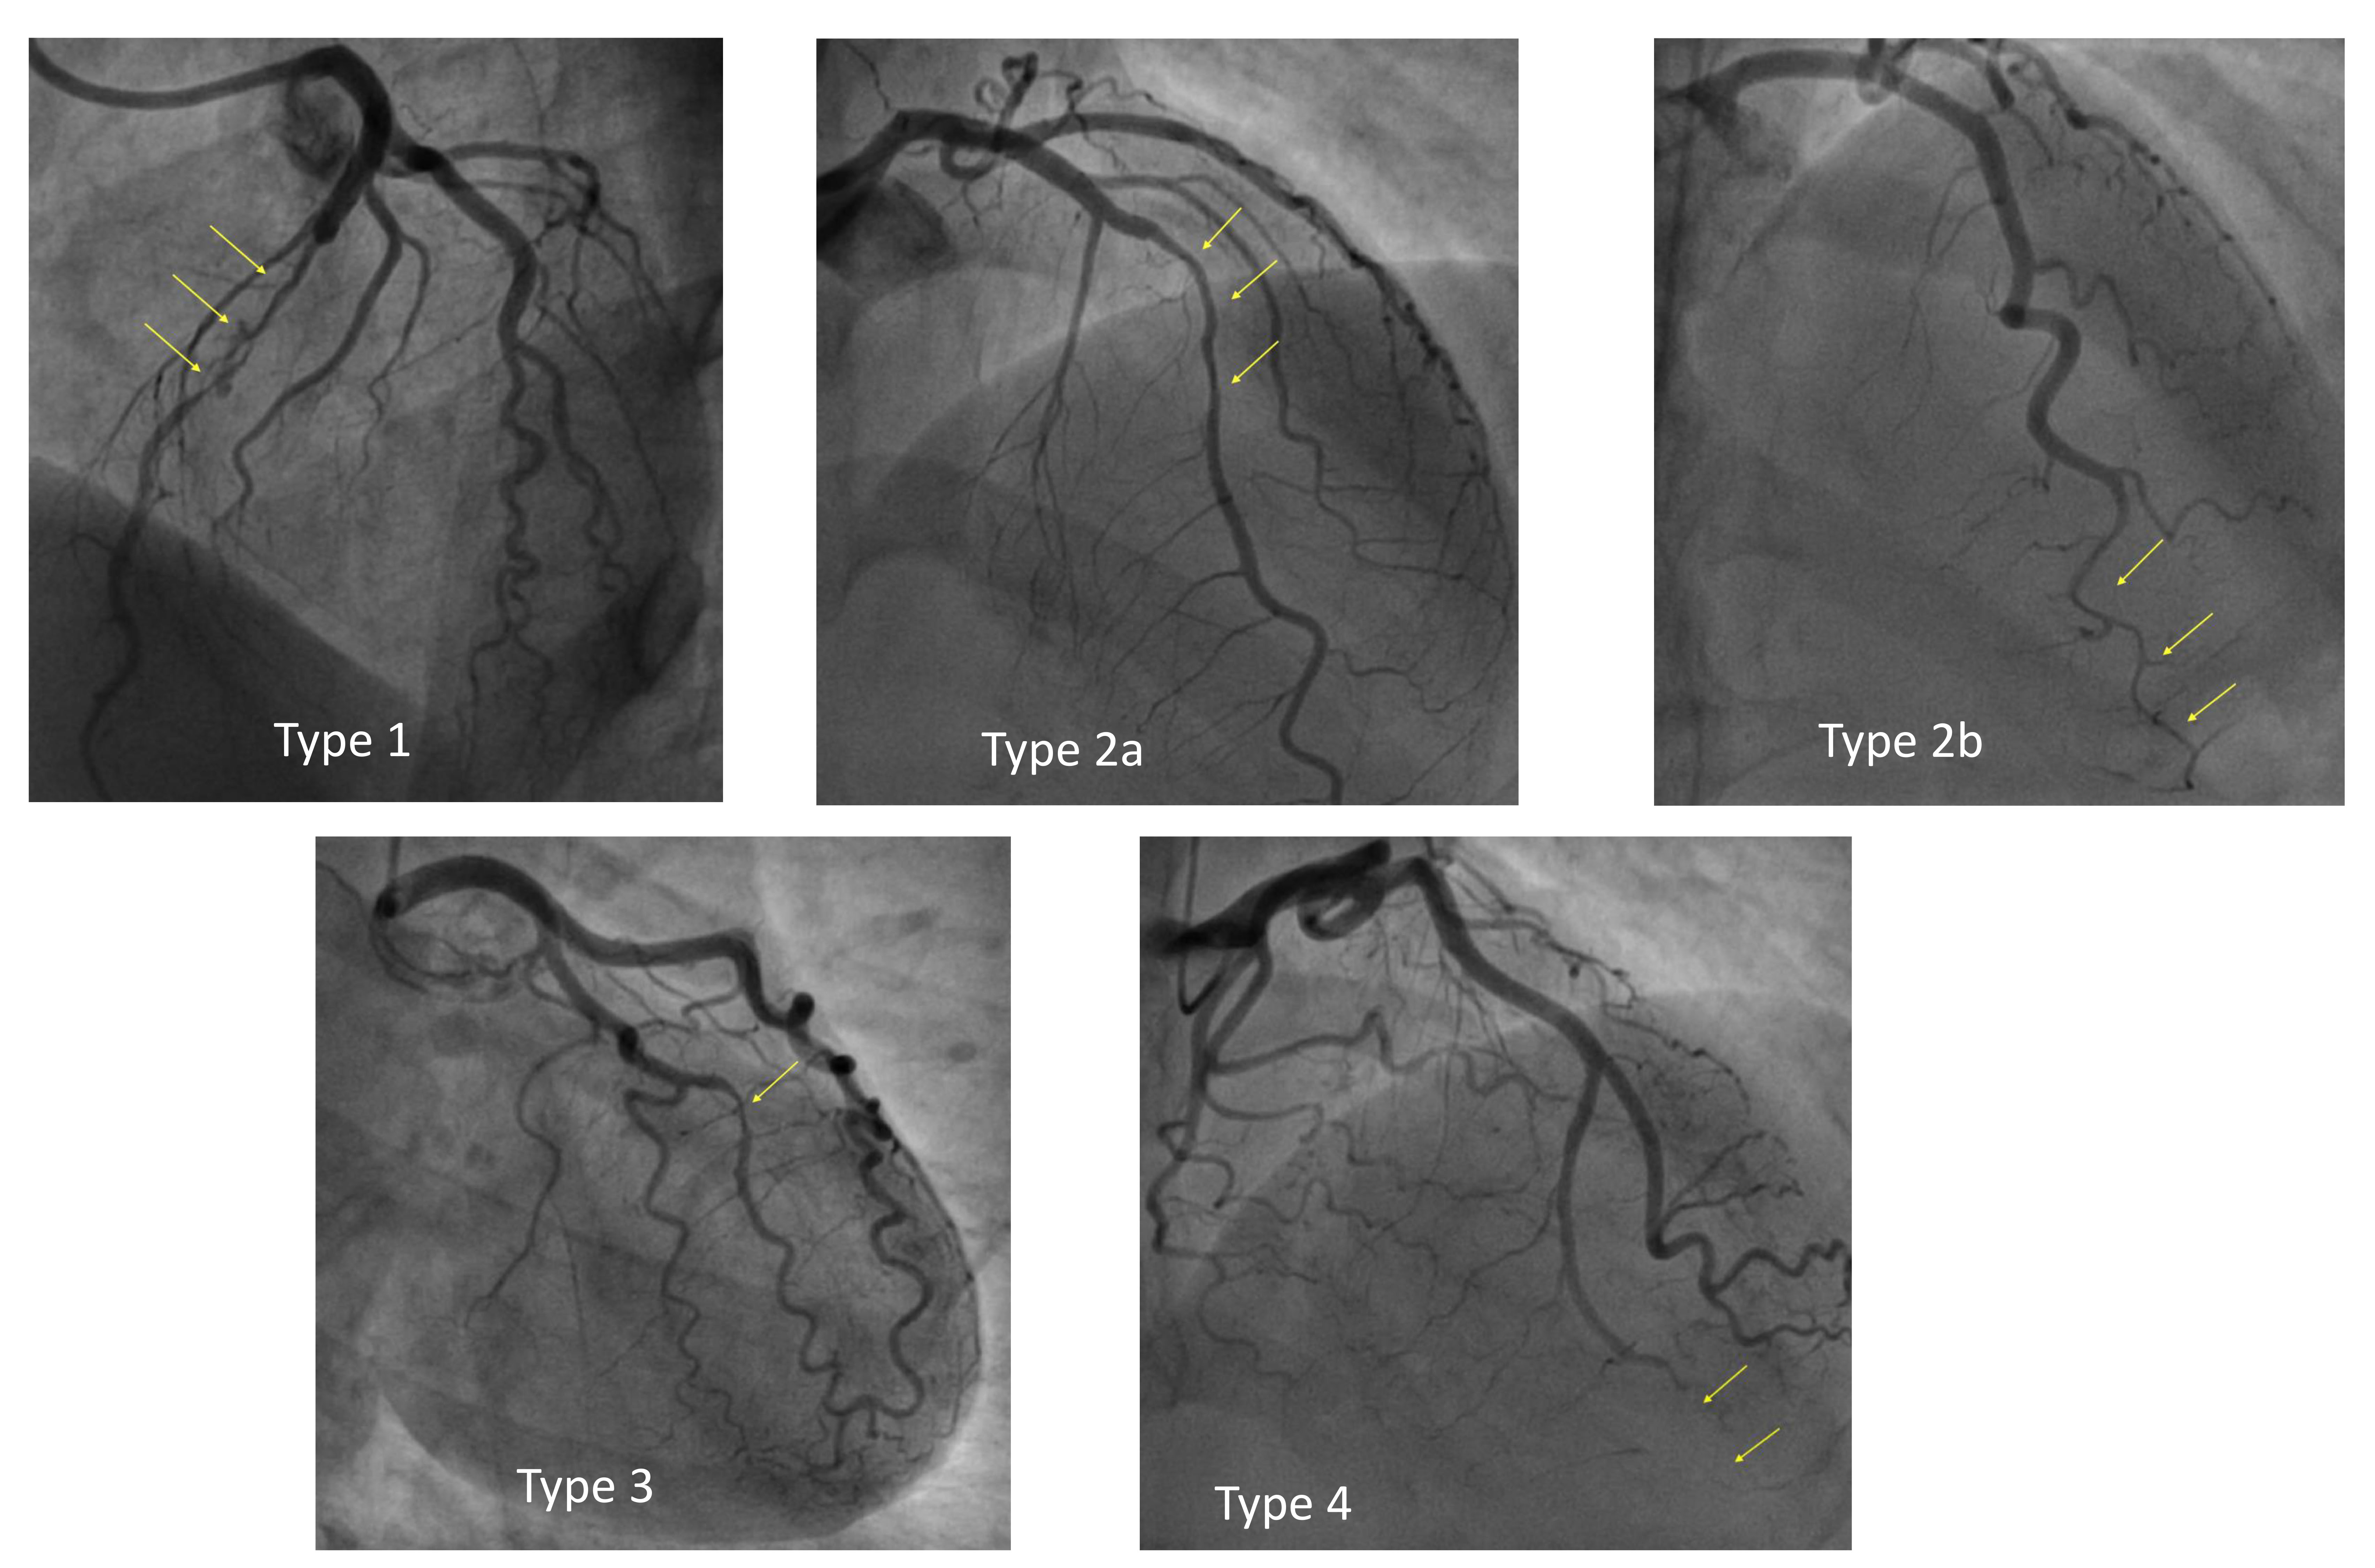

Due to the increased risks of complications and suboptimal results, revascularization should be considered only in high-risk patients, defined according to angiographic and clinical characteristics [46]: persistent chest pain, persistent ST-segment elevation, hemodynamic or electrical instability, proximal location or multiple dissections, left main (LM) dissection, TIMI (thrombolysis in myocardial infarction) 0 and 1 coronary flow. In most cases an interventional treatment is discouraged according to the principle “conservative whenever possible”, yet, in most cases angiographic appearance of multivessel SCAD as well as dissections in proximal segments may lead the operator to perform PCI [47, 48] (Fig. 2).

Fig. 2.

Case 1: Woman, 56 yo, presenting with acute myocardial infarction without ST-segment elevation (NSTEMI). (A) Angiographic presentation (type 1) SCAD of the proximal right coronary artery (RCA) with TIMI 1 flow. (B) Percutaneous coronary intervention (PCI) with implantation of a single Everolimus Eluting Stent due to the angiographic involvement of the proximal segment of RCA. TIMI, thrombolysis in myocardial infarction.

When the option of percutaneous revascularization is considered, a minimalist approach should be followed: the goal of PCI in SCAD should be to restore flow, not to resolve the dissection, which in most cases will heal on its own [49].